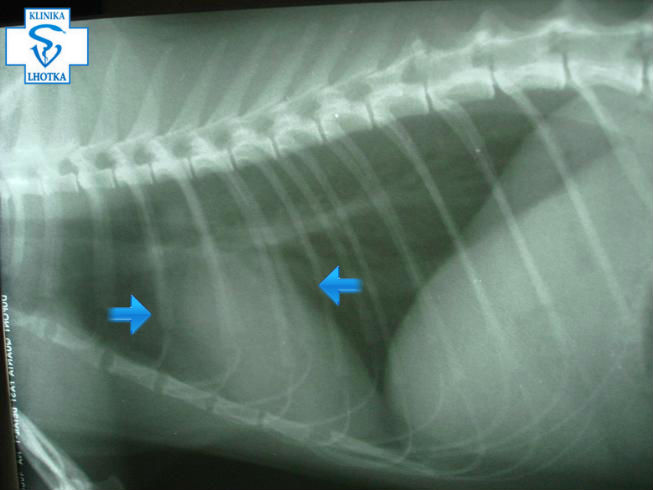

V některých případech nemusí být na RTG-snímcích vidět zvětšení srdce ani změna jeho tvaru  jako u zde prezentovaného kocourka.  Je to dáno  nabýváním  srdeční svaloviny směrem dovnitř ( do centra) srdečních dutin  –  tzv. koncentrická hypertrofie:

RTG-LL-koncentrická hypertrofie u kočky